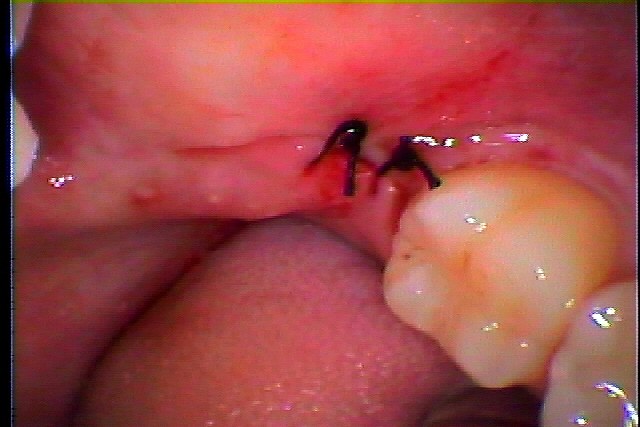

左下親知らずの抜歯 埋伏歯の抜歯|お知らせ |広島市安佐南区の歯科医院 左下親知らずの抜歯 埋伏歯の抜歯 トップ お知らせ・ブログ お知らせ 左下親知らずの抜歯 埋伏歯の抜歯 左下親知らずの抜歯 埋伏歯の抜歯 ここに埋まっている親知らずが腫れるとのこと 埋まっている親知らずを抜歯していきます こんな感じで埋まっています 麻酔をかけて開けていきます 動かないので分割してみます このように抜歯しました 縫合して終了となります腫れるかもしれません 腫れるかもしれません Web診療予約 初めての方へ 選ばれ続ける理由 院内設備について 歯が痛いしみる一般歯科 歯がぐらぐらする歯周病 健康な歯を保ちたい予防歯科 子供の虫歯予防をしたい小児歯科 銀歯をセラミックに審美歯科 白い歯を目指しませんか?ホワイトニング 矯正専門医がいるので安心矯正歯科 抜けた歯を補いたいインプラント・入れ歯 医院案内 スタッフ紹介 メリィハウス歯科クリニックオフィシャルホームページ ラベンダー歯科クリニックオフィシャルホームページ お知らせ・ブログ ホーム 診療科目 一般歯科 歯周病治療 予防治療 小児歯科 審美治療 ホワイトニング 矯正歯科 入れ歯・インプラント マウスピース矯正 初めての方へ 院長・スタッフ 設備紹介 医院案内・アクセス メニューを閉じる